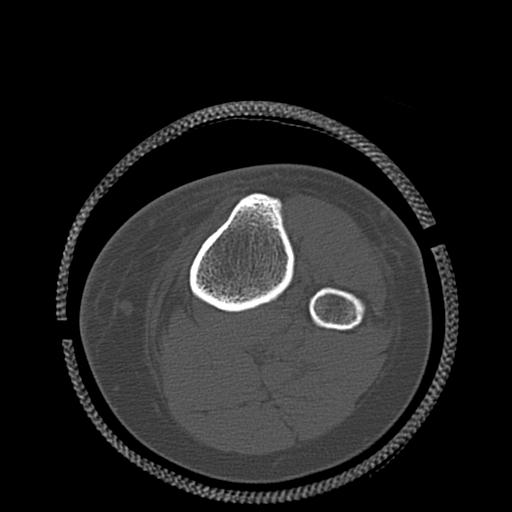

102803 1/12(キウスなし) 1/27 左下腿 4R 30歳女性 左脛骨軸内釘